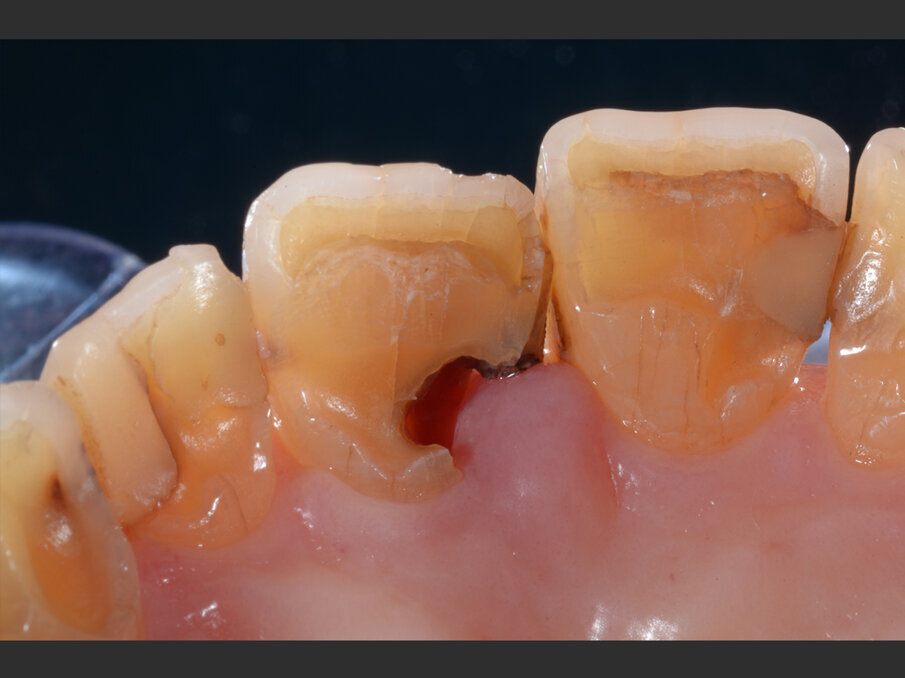

La paziente, donna di 60 anni, non fumatrice ed in buone condizioni di salute generale, si presenta in studio con sintomi di pulpite irreversibile a carico dell’elemento 1.1. L’esame clinico (Figg. 1a, 1b) e radiografico (Fig. 2a) confermano la presenza di una lesione cariosa radicolare che ha colpito il versante mesiale.

Fig. 1a - Valutazione pre-operatoria - visione frontale: l’elemento 1.1 è sintomatico e mostra segni e sintomi di pulpite irreversibile.

Fig. 1b - Valutazione pre-operatoria - visione palatina: è possibile apprezzare la lesione cariosa corono-radicolare.